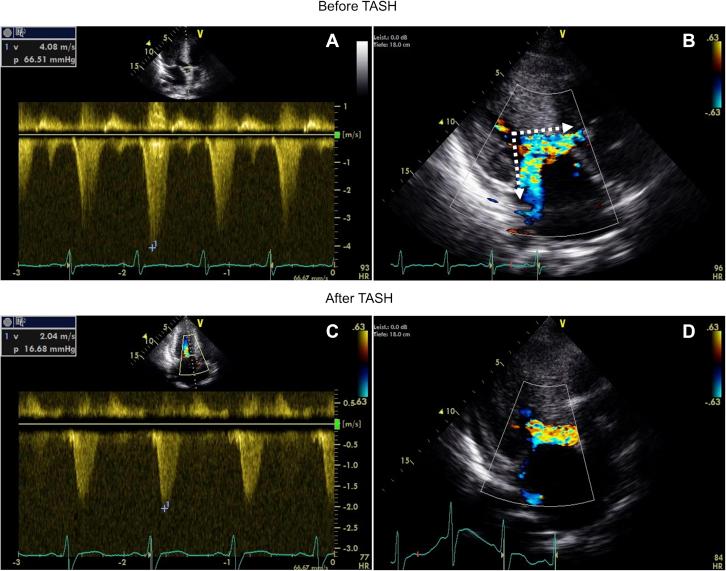

Two Hearts at Risk: Emergency Alcohol Septal Ablation in a Pregnant Woman With Decompensated HOCM.

Hypertrophic obstructive cardiomyopathy (HOCM) increases the risk for mother and fetus during pregnancy. Alcohol septal ablation (ASA) is an established procedure in nonpregnant patients with HOCM. In this report, we present a case of a 29-year-old woman in her 29th gestational week with decompensated HOCM undergoing a successful ASA. ().